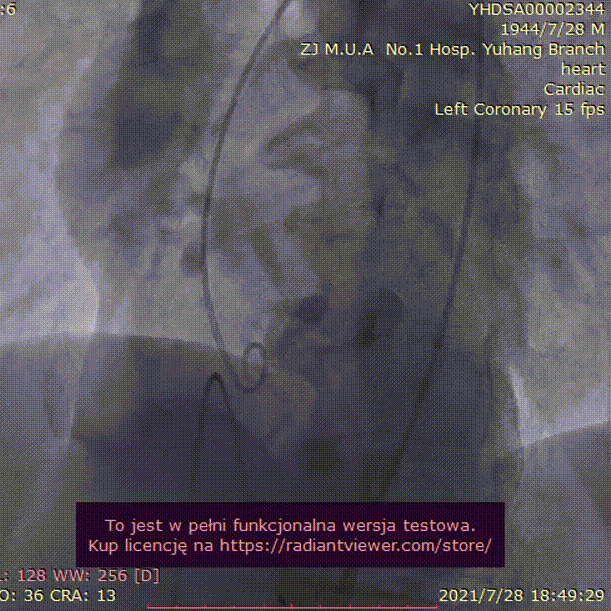

手术过程:

23mm球囊预扩

(有腰征,无瓣周漏,右冠开口阻塞)

TAV24 瓣膜释放前定位

释放4.0*30mm烟囱支架

植入后造影

术后压差1mmHg

术中经食道心超评估: